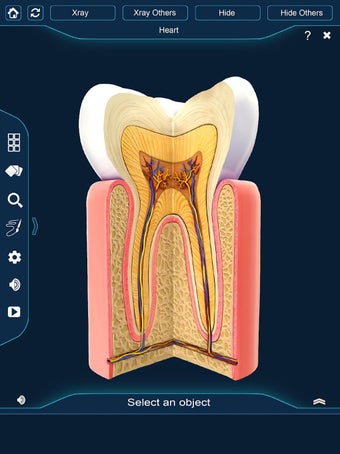

Esta aplicación es un modelo 3D de los dientes, que contiene muchas partes y muestra las condiciones dentales. Cada parte tiene un nombre y una función. Puedes mover la cámara alrededor del modelo para obtener una vista de 360° de las diferentes partes. Puedes hacer zoom para ver mejor cada parte. También puedes rotar la cámara para obtener una vista diferente del modelo.